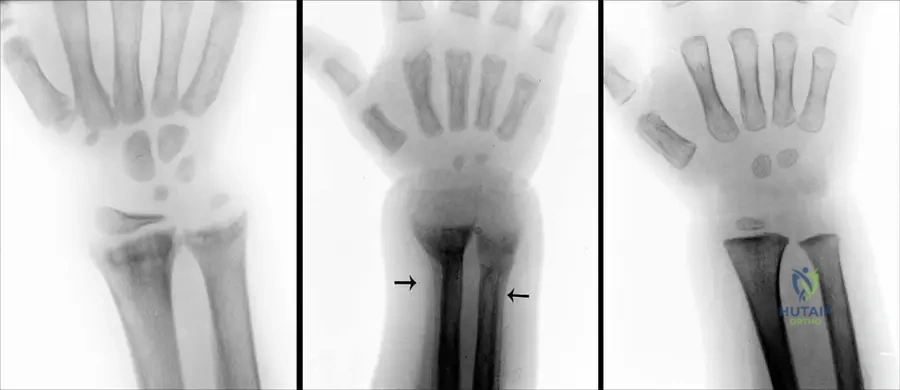

A 7-year-old boy presents with short stature, bowing of the forearms, and atypical clubfeet. Genetic testing is performed to confirm the diagnosis of Nievergelt type mesomelic dwarfism.

View Answer & Explanation

Correct Answer: C

Rationale: The text states that Nievergelt and Langer type mesomelic dwarfism is "caused by mutations in the SHOX gene." FGFR3 mutations are associated with achondroplasia, a common rhizomelic dwarfism, making it a plausible distractor for general dwarfism knowledge.

Question 41

A 7-year-old girl is diagnosed with mesomelic dwarfism, Nievergelt type, characterized by severe shortening of the forearms and lower legs, radio-ulnar synostosis, and atypical clubfeet. Genetic testing is recommended.

Rationale: The case text explicitly states that mesomelic dwarfism (Nievergelt and Langer Type) is "caused by mutations in the SHOX gene."

Question 43

A 12-year-old male with a known diagnosis of mesomelic dwarfism (Nievergelt type) presents for orthopedic evaluation. Clinical examination reveals limited forearm rotation. Radiographs of the forearm are obtained.

Rationale: The case text lists "radio-ulnar... synostosis" as a characteristic feature of mesomelic dwarfism (Nievergelt and Langer Type). Radio-ulnar synostosis directly causes limited forearm rotation (pronation/supination).

Main Distractor: A) Radial head dislocation - While possible in some skeletal dysplasias, radio-ulnar synostosis is specifically mentioned as a defining feature in the text and directly explains the limited rotation.